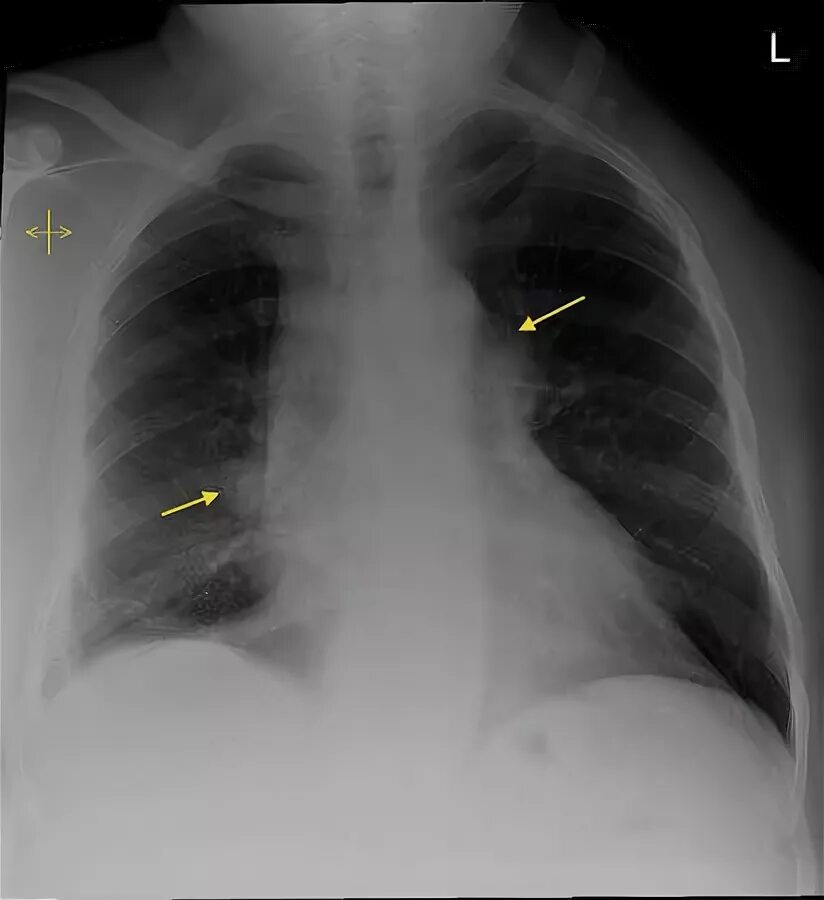

Синдром лефгрена